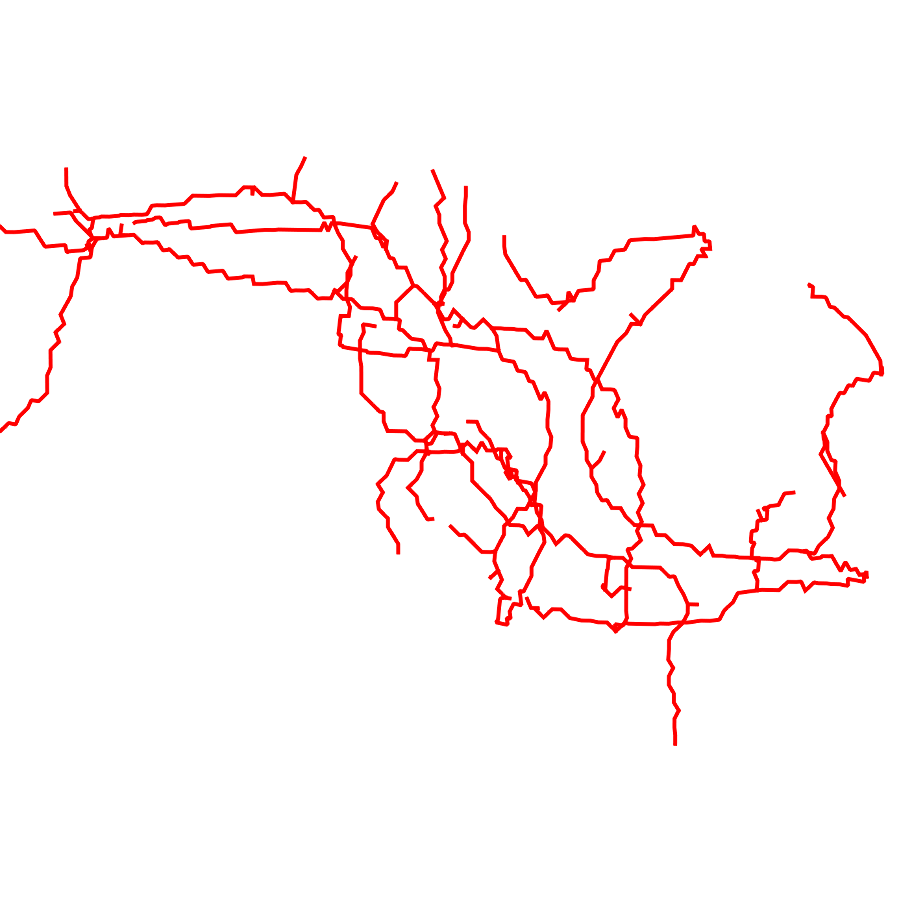

3.2 Connected Geodesic Paths as Vascular Tree

Representative examples of degraded synthetic images from SVT and the respective GT are shown in fig. 4 together with the connected graphs extracted by VTrails. Analogously, the same set of images are reported for the real images TOF and CTA in fig. 4. Qualitatively, the extracted set of connected geodesic paths shows remarkable matching with the provided GT in all cases. First, we verify the acyclic nature of the graph. We found no cycles, degenerate graphs and unconnected nodes, meaning that the extracted connected geodesic paths represent a connected geodesic tree. Precision and recall are then evaluated for the identified branches. Also, error distances are determined as the connected tree’s binary distance map evaluated at GT. Average errors () precision and recall are reported (meanSD) in table 1. Note that no pruning of any spurious branches is performed in the analysis.

| Synthetic Vascular Trees (SVT) [10] | Clinical Angiographies | ||||||

| Image | GT | VTrails | Image | GT | VTrails | ||

| N1 |  |

|

|

CTA |  |

|

|

| N2 |  |

|

|

TOF |  |

|

|